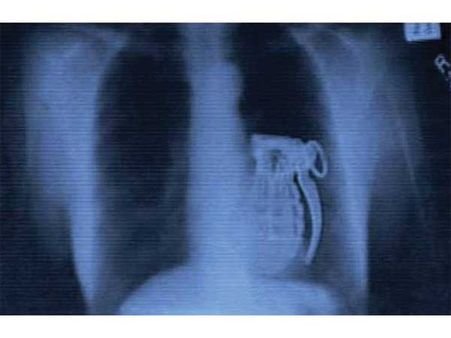

Hand Grenade

Wonder what did this terrorist even think of while placing the hand grenade in his abdomen. Apparently, he was not a good thinker, as he had no means of access to defuse the bomb!